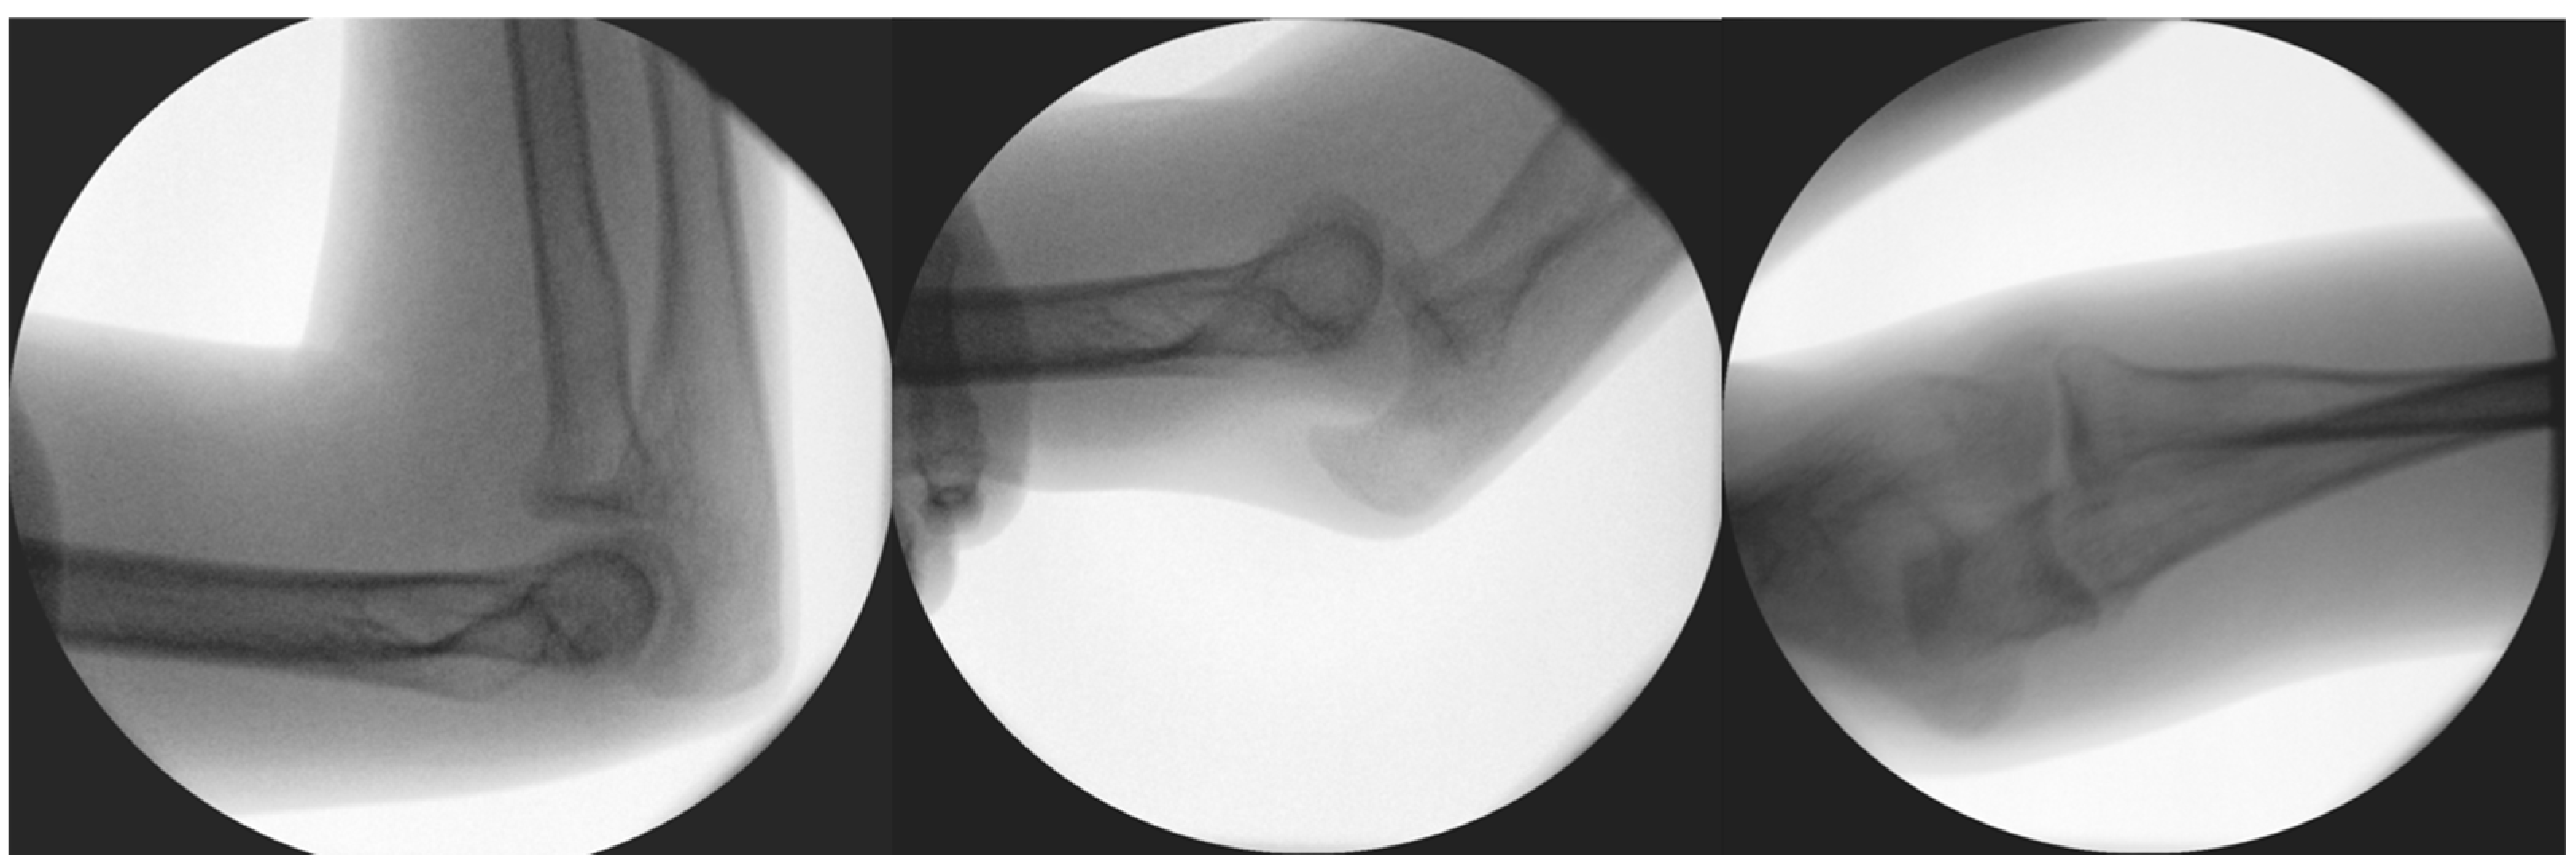

In 2020, her elbow dislocated once again when she was climbing onto her bed. In 2020, on the 1 October, she suffered a fall after she was pushed during a sports activity but had only pain and no dislocation, so she received a splint. A few days later, on the 7 October, spontaneous subluxation of the elbow occurred while the child was getting dressed. We applied a dorsal cast to prevent the extremity from suffering further dislocations and planned further static and dynamic diagnostic tests to evaluate the cause of the recurrent dislocations, as the root cause could not be identified on the initial CT or X-ray images that were provided in 2019 (Figure 2).

Figure 3. Results of diagnostic dynamic testing under fluoroscopy.